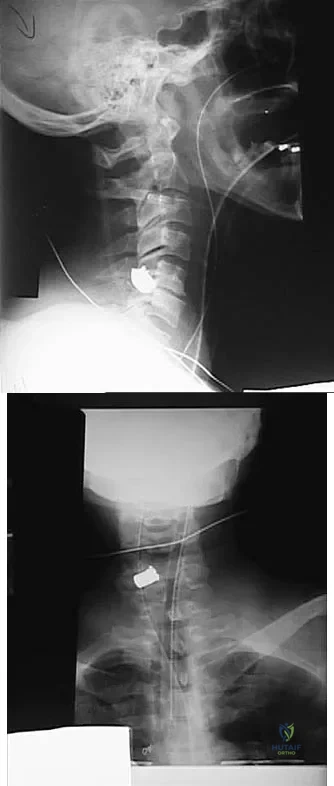

Question 31

Figures 20a and 20b show lateral and AP radiographs of a 49-year-old man who sustained a gunshot wound through the left shoulder. He reports neck pain and examination reveals weakness in all four extremities. What is the priority of evaluation?

Explanation